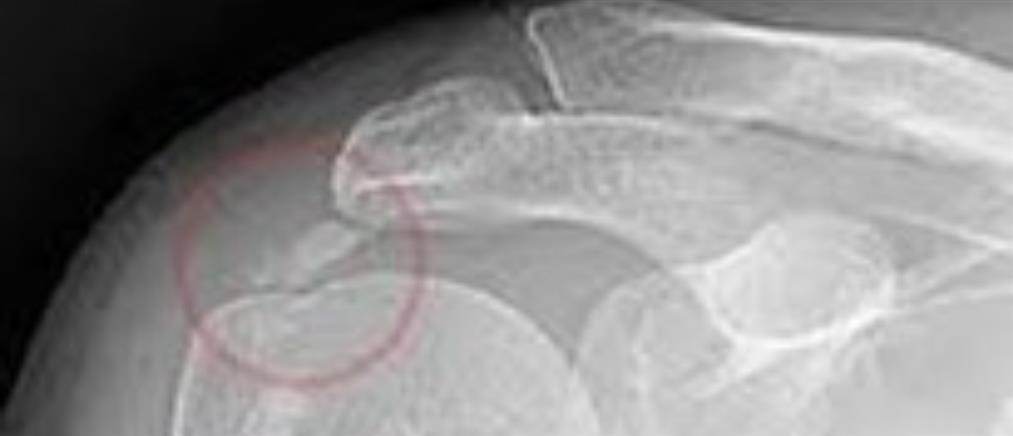

Η διαδερμική δισκοπλαστική στην αντιμετώπιση της οσφυϊκής κήλης του μεσοσπονδύλιου δίσκου